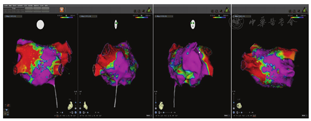

行电复律治疗后,在窦律下采用Carto3系统对患者进行左心房基质标测。如图3所示,消融带连续、完整,且损伤面积覆盖整个前庭区域(红色区域为消融后的低电压区,紫色区域为健康心房肌),占左房后壁面积的80.58%。